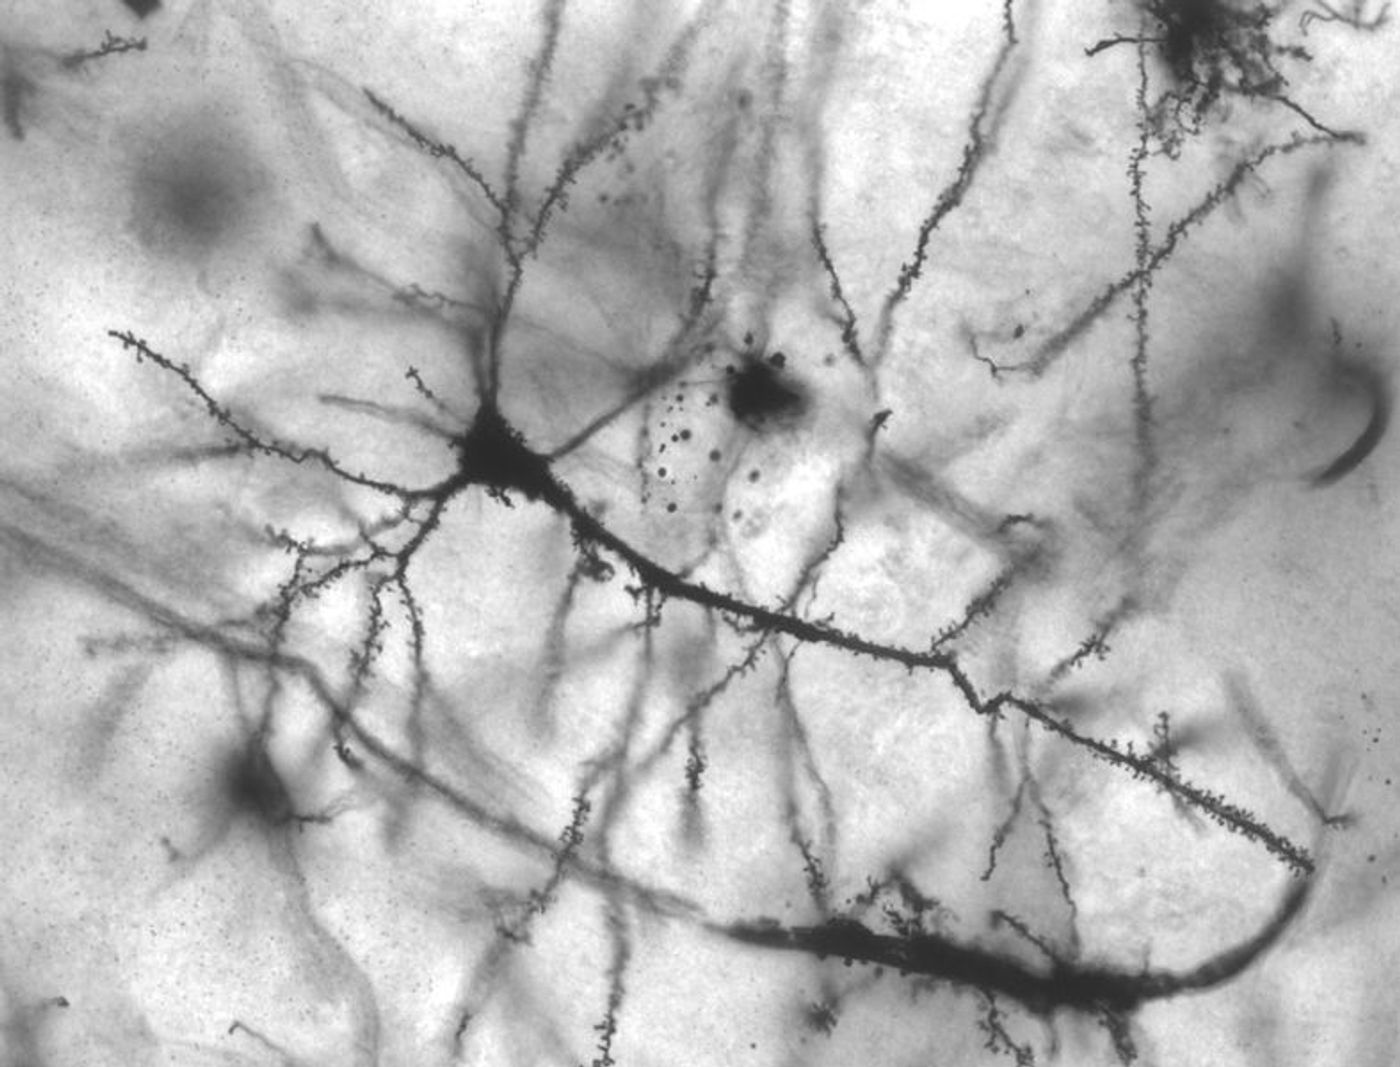

Golgi stained pyramidal neuron in the hippocampus of an epileptic patient. Credit: MethoxyRoxy